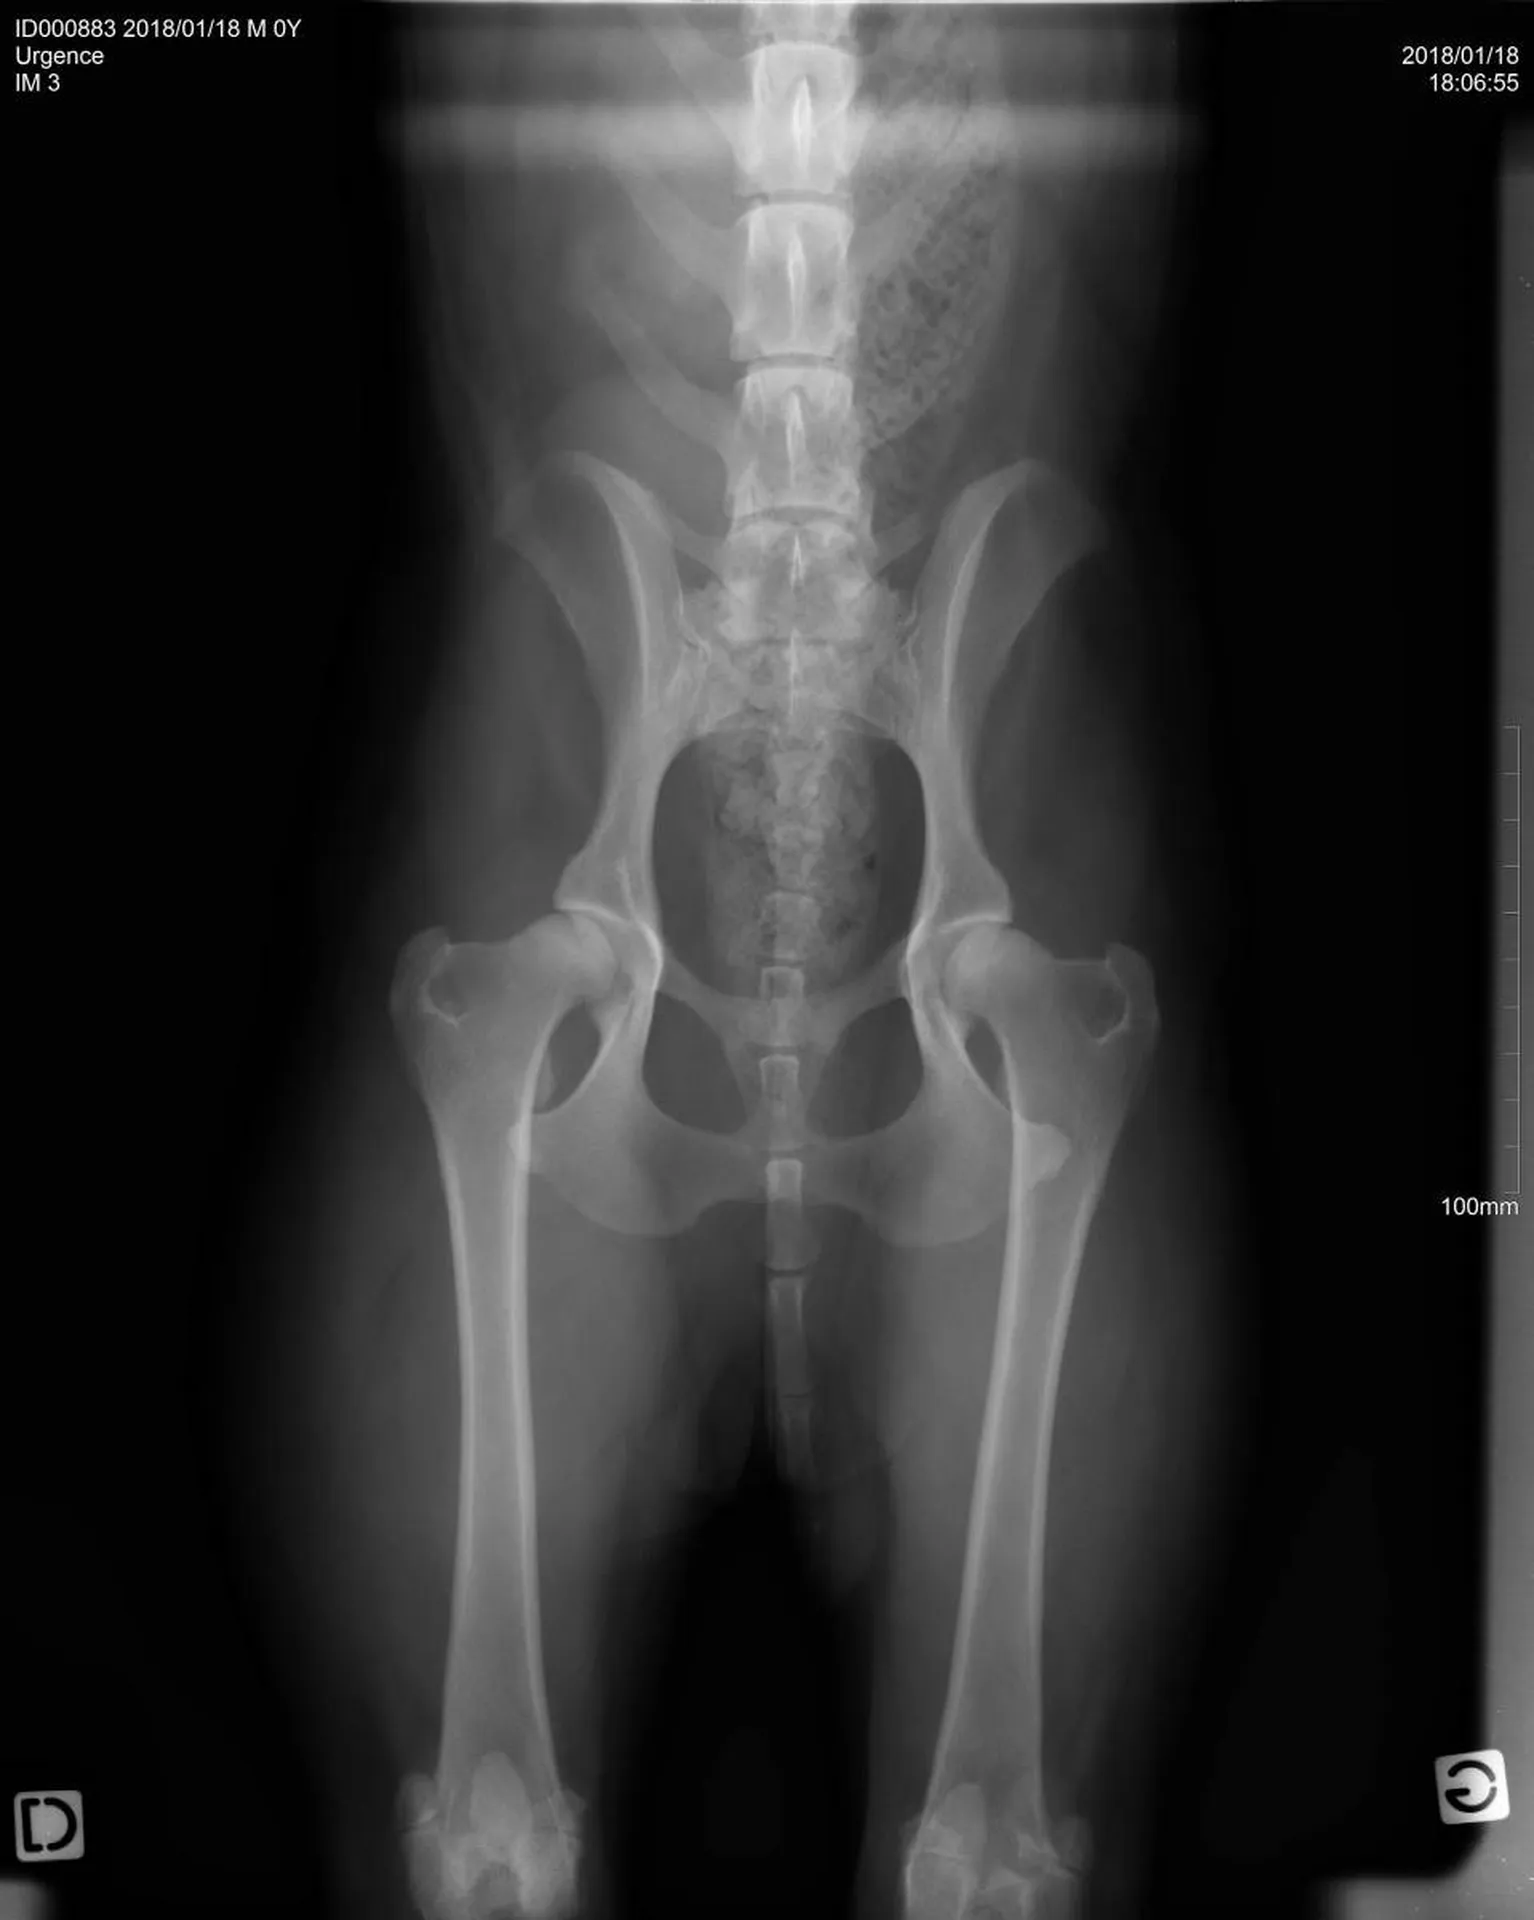

Une radiographie est un examen d’imagerie consistant à la prise de cliché au moyen d’un appareil à rayon X ceci afin de visualiser les différentes structures internes.

La radiographie reste indiquée dans de nombreuses affections, quelles soient respiratoires (radiographie cervicale ou thoracique), digestives (radiographie thoracique ou abdominale), locomotrices (membres, colonne), dentaires.

Votre chien, chat Nac est déposé sur la table de radiologie et différents clichés sont effectués dans différentes positions suivant la pathologie présentée.

Certains clichés demandant des positions particulières (hanches, sinus, dents), une anesthésie peut être nécessaire afin de procéder à cet examen. La clinique vétérinaire du Las saura vous conseiller et vous avertir si cela est envisagé.

Comme tout examen, il présente ses limites. Le principe de la radiographie étant l’utilisation du contraste (visualisation d’un tissu par rapport au tissu environnant et par rapport à sa radiodensité), certaines pathologies ne peuvent être que suspectées par radiographie mais nécessite d’autres examens (échographie, endoscopie, scanner, IRM).